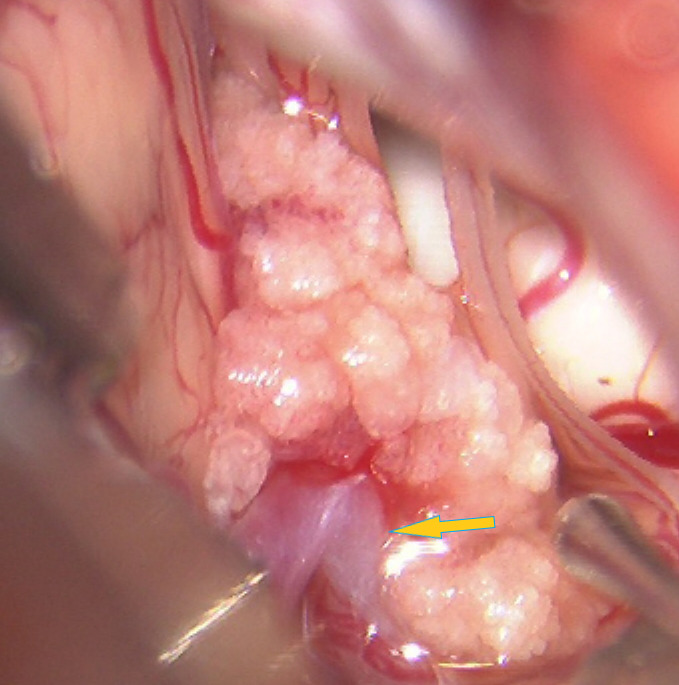

三叉神経痛右顔面の非常に強い痛みがあり、薬が効かないということで4月に来院されました。

MRIで右三叉神経に血管が接触しているのを確認し、開頭術を行いました。

三叉神経(白)が血管(赤)により強く圧迫されていました。